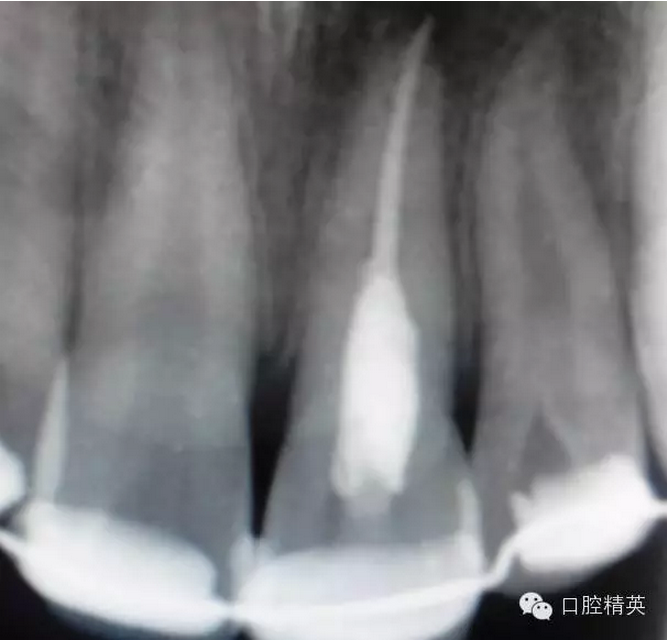

x線檢查:21牙槽窩空虛,窩內(nèi)未見(jiàn)其他遺留物。

圖3.患者21根尖片,牙槽窩空虛,無(wú)變形。